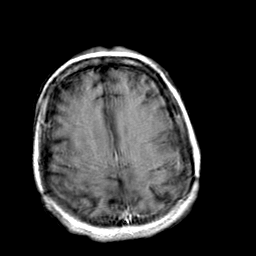

Creutzfeld-Jakob disease: gadolinium enchanced T1-Weighted MR -- Slice #17

[Home][Help][Clinical] Slice 17